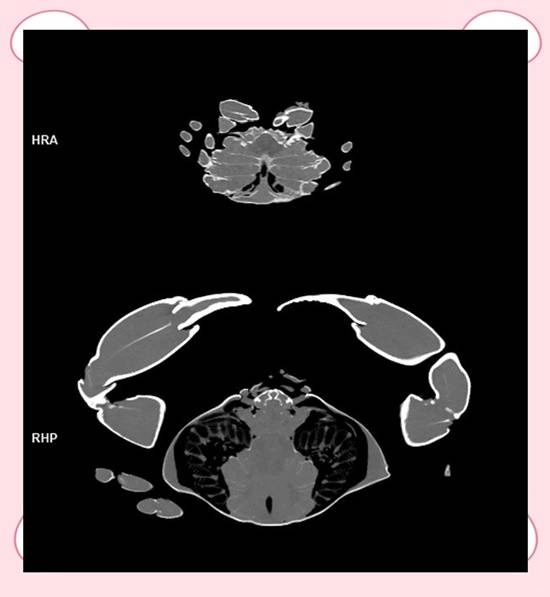

据现代快报消息,近日,江苏苏州的ACE绿舟宠物医院在社交平台上发布了一则“用CT扫描大闸蟹”的视频,该视频迅速吸引了众多网友的目光。

视频画面中,工作人员把整盒的阳澄湖大闸蟹逐个摆放整齐,利用医用CT设备对其进行扫描成像,最后清晰地展示出了螃蟹的内部构造。

宠物医院的工作人员向@现代快报 记者介绍,CT设备原本就能用于检查动物的内部构造,刚好他们手头有一盒大闸蟹,于是尝试用CT进行了扫描。“由于蟹肉和蟹黄的密度存在差异,所以能够清晰成像。”